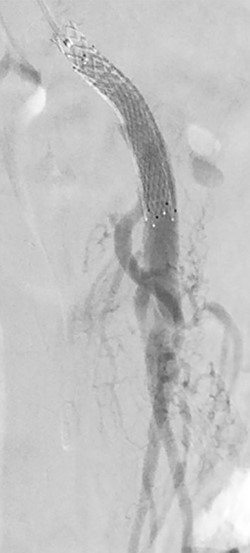

She was admitted and maintained on bowel rest and heparin infusion. Given persistent pain after 2 days of non-operative management, an abdominal arteriogram was performed through a left axillary artery cutdown. The dissection was identified 1.5 cm distal to the origin of the SMA (Fig. 2). Intravascular ultrasound was used to determine diameters and landing zones for stent placement (Fig. 3). The dissection was initially treated with a 6 mm × 40 mm self-expanding stent followed by post-dilation with 4 mm × 40 mm and 6 mm × 40 mm balloons. A 5 mm × 19 mm stent graft was deployed proximally with small overlap and ~3-mm extension into the aorta. Completion angiogram showed <10% residual stenosis (Fig. 4). As the right external iliac artery dissection was small and asymptomatic, no intervention was performed.

Pre-stenting angiogram of the SMA demonstrating early filling of the false lumen including the middle colic artery.

Post-stenting angiogram of the SMA demonstrating preservation of the middle colic artery as well as the distal branches of the SMA.